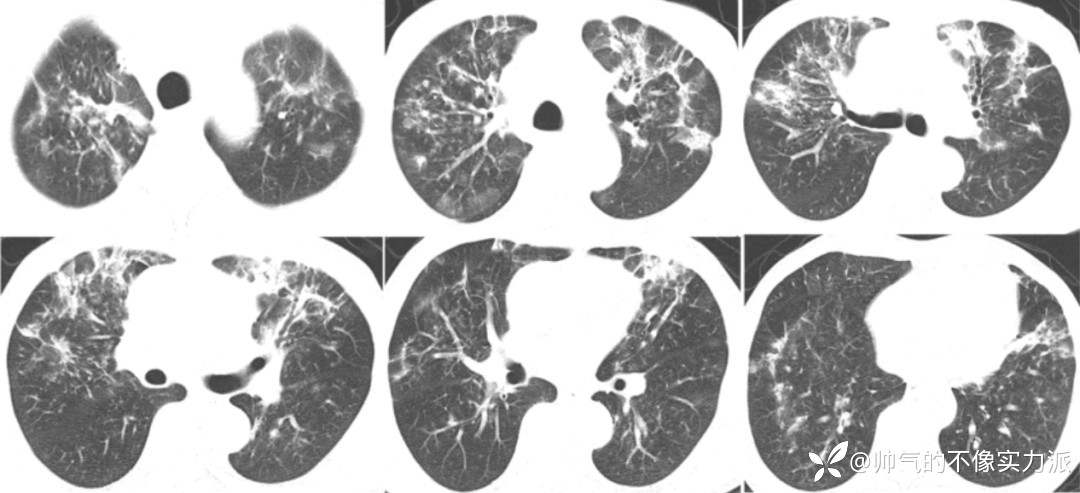

- 2020年12月12日,复查胸部CT:双上肺磨玻璃影明显增多,下肺重力依赖区依然存在实变影,少量胸腔积液(图3)。

图3 患者胸部CT(2020-12-12)

- 复查胸部CT(2020-12-16):双上肺病变仍然较重,双下肺重力依赖区实变影明显吸收,双侧少量胸腔积液(图5)。

图5 患者胸部CT(2020-12-16)

- 2020年12月23日复查胸部CT:双上肺病变明显吸收,遗留少量斑片条索影,双下肺吸收良好(图7)。

图7 患者胸部CT(2020-12-23)